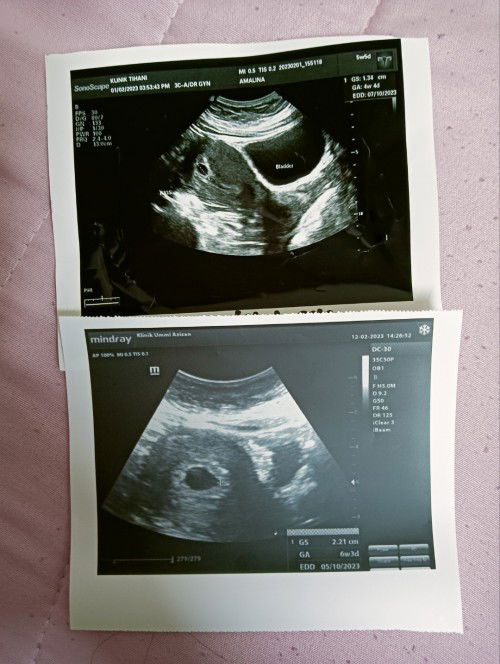

Hi Mommies... Gambar atas tu masa 5w5d,, tp scan kantung 4w4d.. Gambar bawah masa 7w2d (hari ni 12/2/22) tp scan kantung 6w3d.. Normal je kan masih belum ada janin baby... Doc suruh repeat scan lagi 2 weeks.. i'm PCOS fighter.. now 2nd child after 4years... #bantusharing #pleasehelp #advicepls